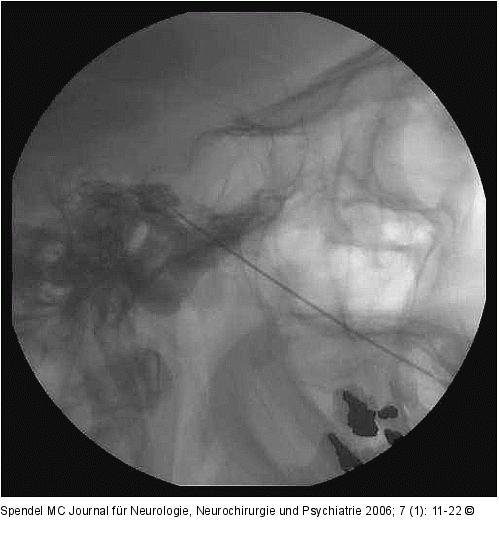

Abbildung 6: Glyzerinrhizolyse - Cavum Meckeli - Zisterna trigemini Glyzerinrhizolyse: Röntgenaufnahme der Schädelbasis seitlich. Nadelspitze im Kontrastmittelfüllung der Zisterna trigemini. |

Glyzerinrhizolyse: Röntgenaufnahme der Schädelbasis seitlich. Nadelspitze im Kontrastmittelfüllung der Zisterna trigemini. |